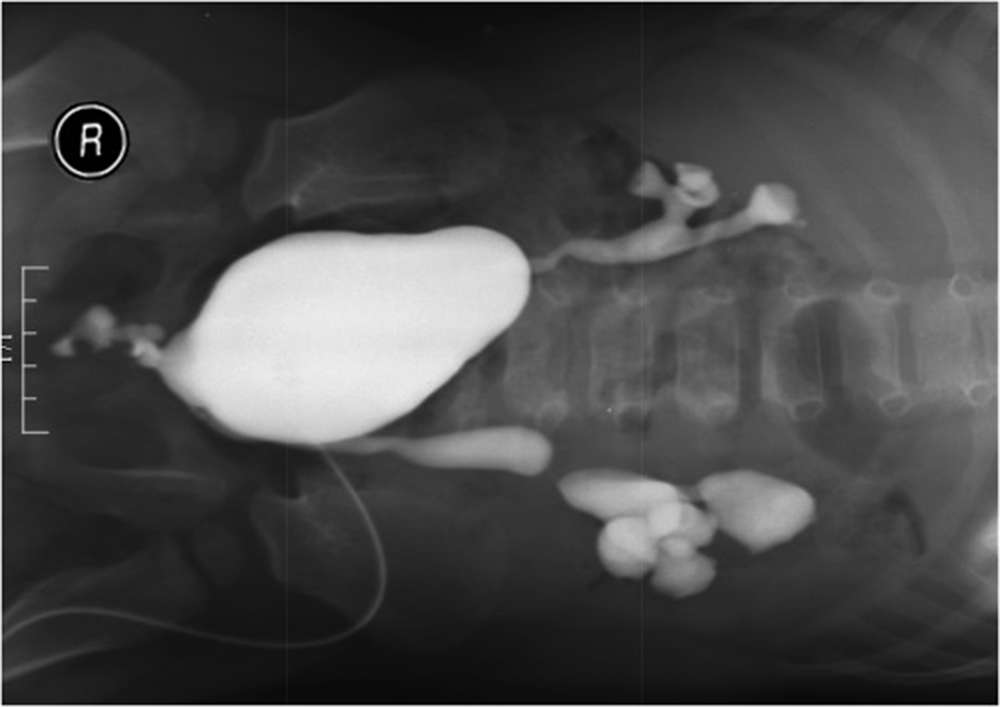

Въпреки че пенисът не е наличен, бебето има оформили се тестиси и скротум. При него обаче са наблюдавани и други проблеми, които обикновено не се срещат при пациенти с подобно състояние. Медицинският екип е открил везико-ректална фистула – анормална връзка между мехура и ректума. Бебето е имало и везико-ректален рефлукс - т.е. когато потокът на урината тръгне в грешна посока. Вследствие на това тя се е натрупвала в мехура му, което е изисквало хирургична намеса.

Натрупване на урина в пациента. Източник: Urology Case Reports (CC BY-NC-ND 4.0)

След операция фистулата е коригирана, а с помощта на катетър пък урината е изведена от мехура. Детето идва на прегледи през един месец и засега е в относително добро здраве. Според лекарите „реконструцията на пениса би била добра алтернатива за този пациент“.